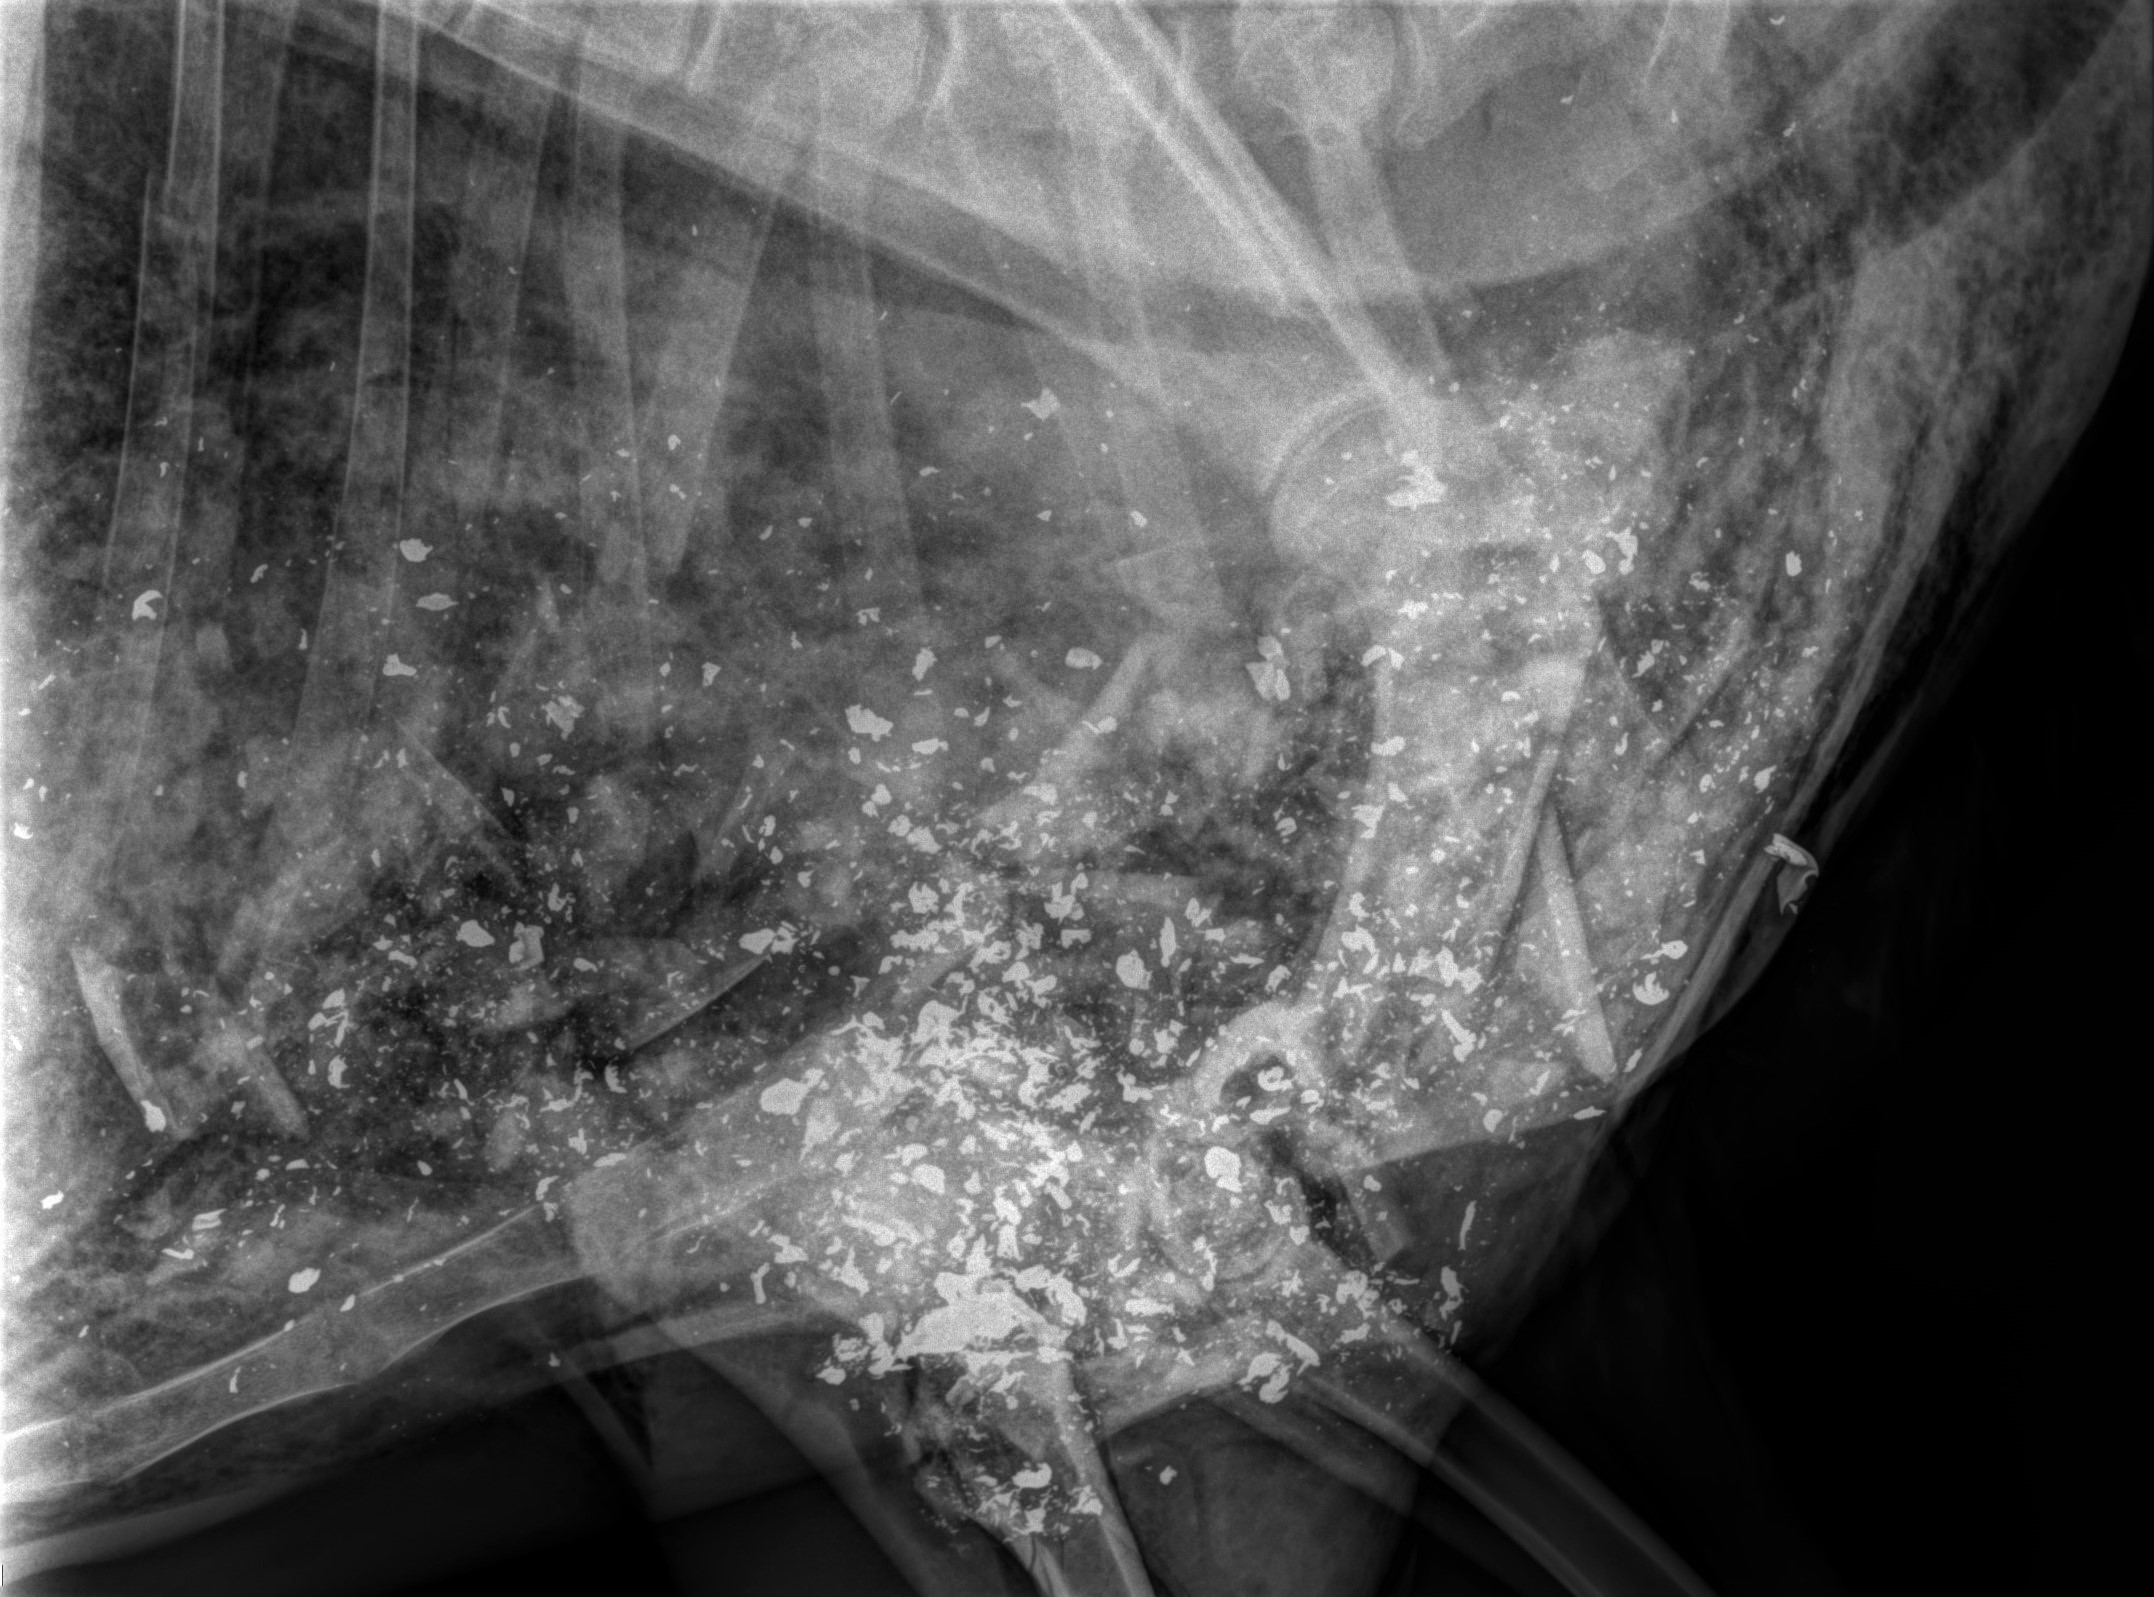

- I sometimes use live fluoro x-ray machines while trying to put people's bones back together when they've been shot. It it AMAZING how far and wide the little bits travel. You can NEVER find them all and I don't like eating that stuff. Here are a few images I stole from the Internet. The first one is a bit extreme but the others aren't so unusual.

View attachment 673001View attachment 673002View attachment 673003View attachment 673004